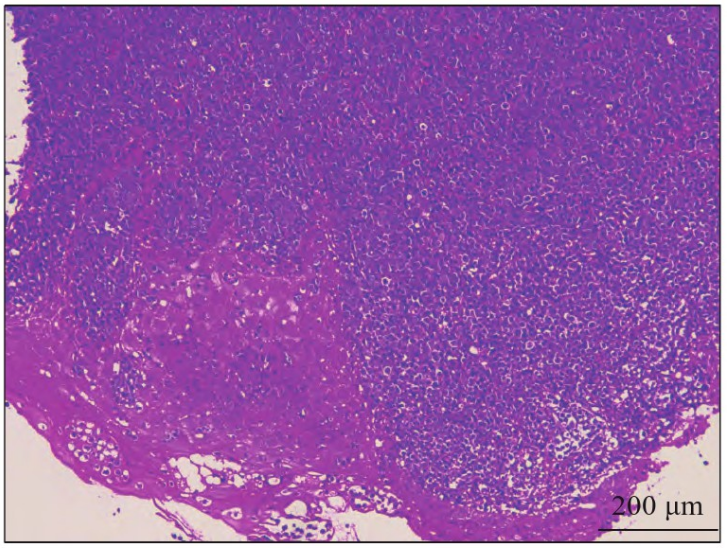

局部麻醉下取活检,HE染色镜下肿瘤淋巴细胞弥漫性生长,细胞大或中等大小,缺乏黏附性,胞质丰富,嗜碱性,可见中位核仁,呈免疫母细胞样细胞(图4);免疫表型:肿瘤细胞CD20、PAX-5、CD79a均弥漫阳性,Ki-67增殖指数约90%,CD10阴性,Bcl-6(图5)、MUM-1阳性,呈活化B细胞(activated B-cell-like,ABC)型,Bcl-2(>80%阳),c-MYC (>40%阳),CK、CD3、CD-5、CD30、CD21、Cyclin D1均阴性;原位杂交EB病毒编码的小RNA (Epstein-Barr virus encoded RNAs,EBER)阴性,c-MYC分离探针FISH检测结果(图6)显示:肿瘤细胞内存在2个黄色信号或2个紧密相邻的红绿信号,提示c-MYC基因未发生断裂。

图4 病例2的HE染色图×400